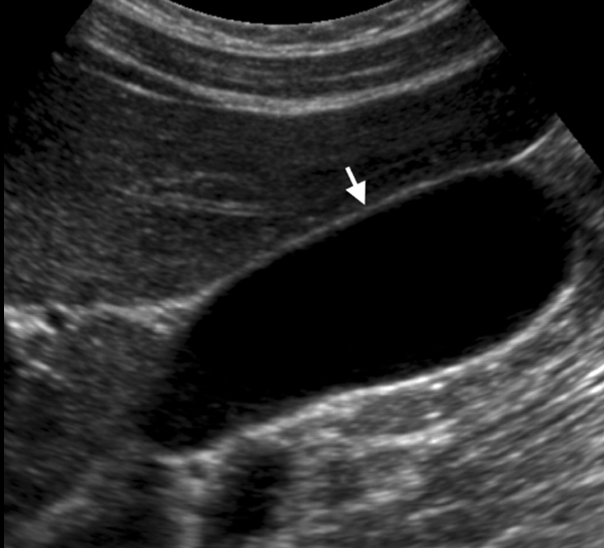

The name of this abdominal US finding.

What is intussussception?